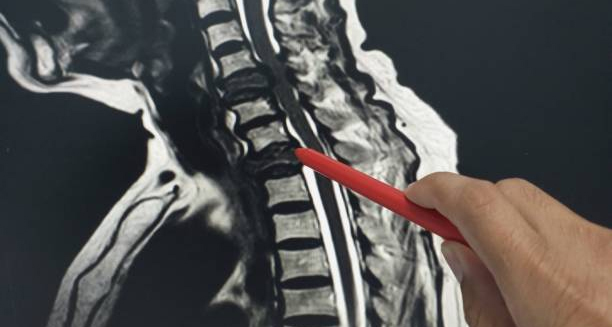

- MRI (Magnetic Resonance Imaging): Provides detailed images of soft tissues, including discs, spinal cord, and nerves — ideal for detecting nerve compression or herniated discs